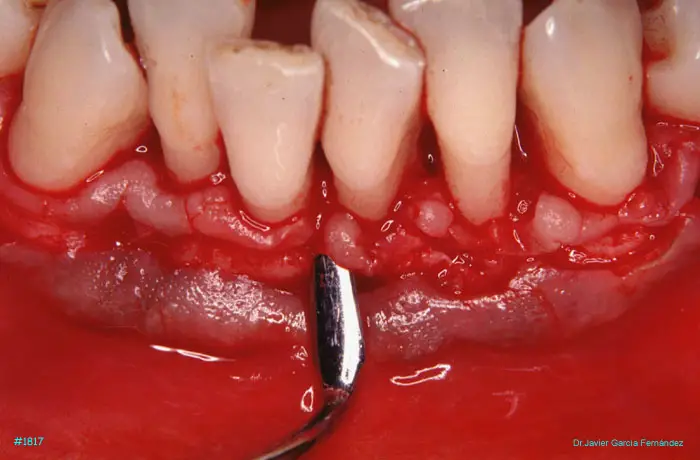

image 84